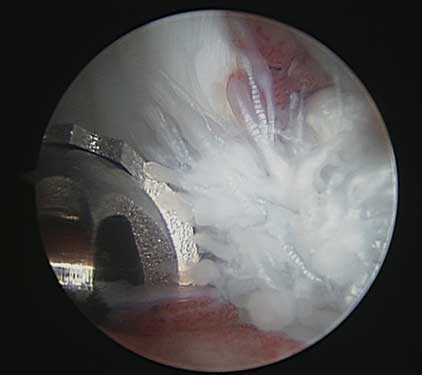

The image to the left is an arthroscopic image looking at a dog’s ruptured (torn) cranial cruciate ligament. It looks like the ends of a mop. On the right we can see that the femur is sliding off the back of the tibia, which is why procedures like TPLO surgery (aka “dog ACL surgery”) are necessary to stabilize the knee after a CCL rupture.